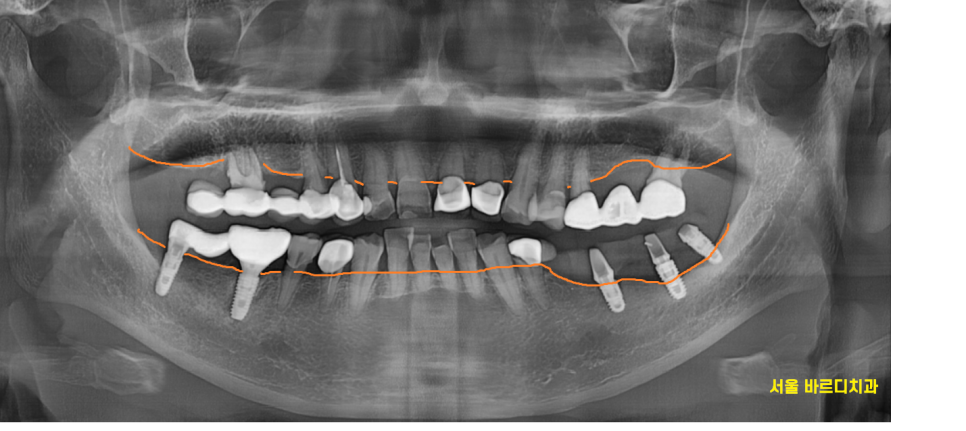

환자분 말씀처럼 치아가 다 부서지고 깨져있네요.

x-ray를 통해 확인해 보니

예전에 임플란트를 심었던 곳인데요.

23.08.23

특별한 점이 있다면 사랑니 부위에도

임플란트가 심어져있었습니다.